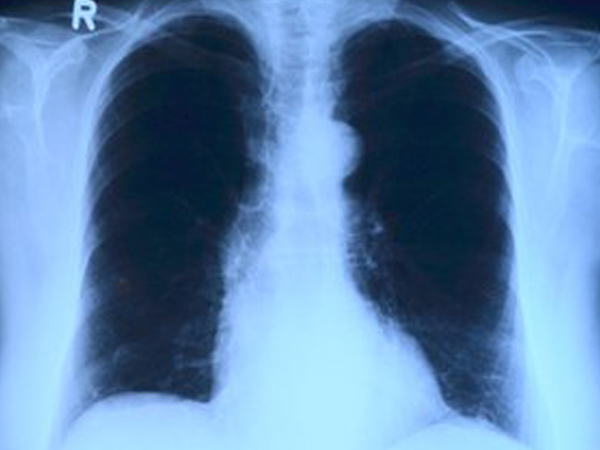

இதுவரை அறியப்பட்டவற்றிலிருந்து, ஒரு வெள்ளை பூஞ்சை தொற்று இயற்கையாகவே மிகவும் கடுமையானதாக இருக்கலாம், மேலும் இது பல அறிகுறிகளை ஏற்படுத்தக்கூடும். கருப்பு பூஞ்சை தொற்று நோய் வெளிப்படுத்தும் முகவீக்கம், பார்வைக் குறைபாடு போன்ற வெளிப்படையான அறிகுறிகளாக இல்லாமல் மருத்துவர்கள் HRCT போன்ற மார்பு ஸ்கேன் செய்வதன் மூலம் மட்டுமே இதனை கண்டறிய முடியும் என்று பரிந்துரைக்கின்றனர்.

இப்போது அதிகளவு நோயாளிகளிடம் காணப்படுவது போல, வெள்ளை பூஞ்சை தொற்றுடன் கண்டறியப்பட்ட பெரும்பாலான மக்கள் COVID-19 ஐ ஒத்த சுவாச அறிகுறிகளைக் கொண்டிருந்தனர், ஆனால் வைரஸுக்கு எதிர்மறையான பரிசோதனை முடிவை பெற்றனர். எக்ஸ்ரே அல்லது மார்பு ஸ்கேன் மட்டுமே நோய் எவ்வளவு கடுமையானது, மற்றும் முக்கிய உறுப்புகள் எவ்வாறு பாதிக்கப்பட்டுள்ளது என்பதை துல்லியமாக கணிக்க முடியும் என்று நிபுணர்கள் தெரிவிக்கின்றனர்.

சுவாச சிக்கல்கள்

இந்த விஷயத்தில் இதுவரை போதுமான தகவல்கள் கிடைக்கவில்லை என்றாலும், பெரும்பாலான மருத்துவர்கள் வெள்ளை பூஞ்சை, மார்பு மற்றும் நுரையீரலைப் பாதிக்கக்கூடும் என்று பரிந்துரைக்கின்றனர், எனவே ஒருவர் இருமல், மார்பு வலி, மூச்சுத் திணறல் போன்ற அறிகுறிகளை பெறலாம். இது தவிர, தொற்று வீக்கம், நோய்த்தொற்றுகள், தொடர்ச்சியான தலைவலி போன்ற பல அழற்சி அறிகுறிகளையும் ஏற்படுத்தும். கூடுதலாக, கொரோனா வைரஸிலிருந்து குணமடையும் நோயாளிகளும் அடிப்படை நிலைமைகள் மற்றும் சிகிச்சைகள் காரணமாக வெள்ளை பூஞ்சை தொற்று அபாயத்தை எதிர்கொள்ளலாம்.